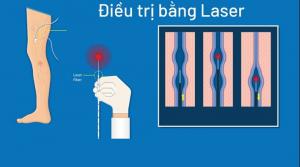

Trong bản khuyến cáo hiện hành, những hướng dẫn về việc sử dụng hệ thống phân loại GRADE làm cơ sở cho việc điều trị bằng VADs. Những khuyến cáo này bắt nguồn từ khuyến cáo trước đó của Perrin và Ramellet,

Liệu pháp xơ hóalà tiêm hay truyền một chất gây xơ hóa vào tĩnh mạch trào ngược để phá hủy nội mô và sợi hóa mạch máu. Tiêm trực tiếp chất gây xơ vào tĩnh mạch thường dành cho các tổn thương mao mạch (telangiectatic lesions) hơn là CVI. Gây độc tĩnh mạch (phlebotonics) chưa được chứng minh có ích trong điều trị suy tĩnh mạch mạn tính.

Suy tĩnh mạch không phải là không phổ biến hay không lành tính. Điều trị nhằm giảm triệu chứng và điều chỉnh các nguyên nhân nền nếu có